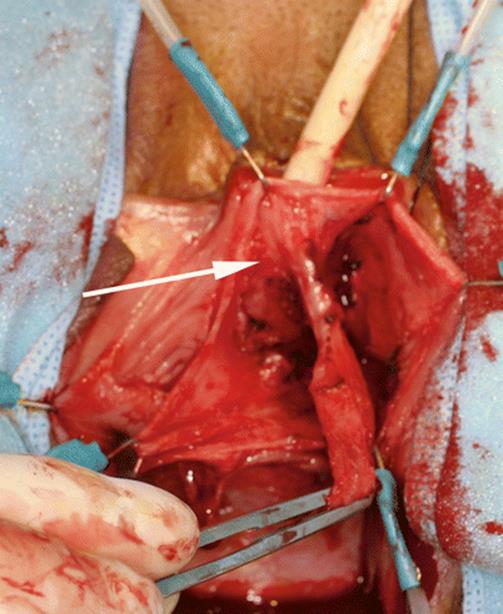

8.3 Ectopic Ureterocele Presenting as a Vaginal Cyst

The patient, 23 years old, presented with difficulty in emptying the bladder, recurrent urinary infection, and distal urethral pain. Figures 8.11, 8.12, 8.13, and 8.14 illustrate the finding of an ectopic ureterocele. The patient had a side-to-side anastomosis of the ureters, with ligature of the affected ureter. The urethral cyst and her voiding dysfunction were corrected and she remained asymptomatic.

Fig. 8.14

A post-void film shows a large cystic filling defect of the bladder base, typical of an ectopic ureterocele. The arrows outline the cyst